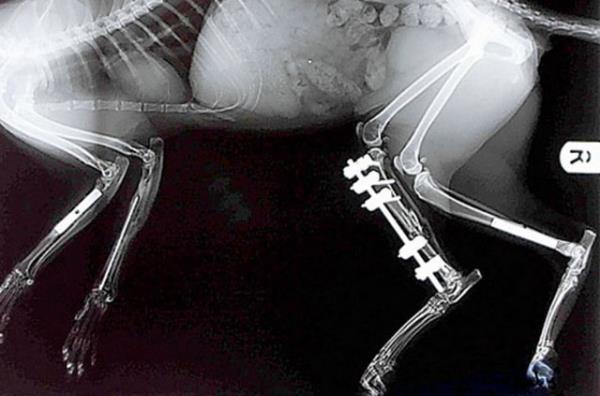

17. Londra'da yaşayan bu yavru kedinin röntgeninde ise bacağına takılan platin gözüküyor.

Londra'da yaşayan bu yavru kedinin röntgeninde ise bacağına takılan platin gözüküyor.